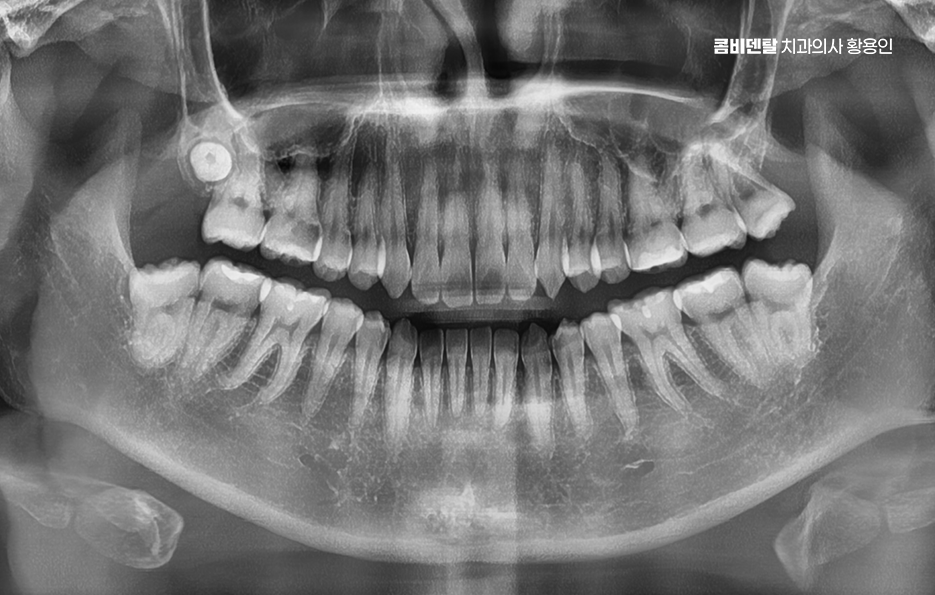

명동치과 그런데 문제는 이 두 부위에 생긴 충치나 손상이 단순히 그 치아만의 문제가 아니라, 주변 치아 등에도 영향을 줄 수 있다는 점에서 원인을 제대로 알고, 그에 맞는 해결 방법을 빠르게 선택하는 게 중요한데 먼저 사랑니는 맨 뒤쪽에 위치한 제 3 대구치로 대부분 10대 후반에서 20대 초반 사이에 맹출하기 시작하며 공간이 부족하거나 방향이 비정상적인 경우가 많아서 완전히 나오지 못하고 잇몸이나 턱뼈 안에 매복되는 경우도 많이 있어요

이런 사랑니는 주변에 음식물이 잘 끼고, 칫솔이 닿기 어려워서 충치나 잇몸 염증이 쉽게 생기는 구조로 특히 반쯤 나온 사랑니는 위생관리가 특히 어렵다 보니 조금만 방심하면 바로 통증과 붓기를 동반한 염증으로 이어지는 거예요.

명동치과 게다가 사랑니의 위치가 문제인데 맨 뒤에 있기 때문에 일반 칫솔로 닦기 어렵고 양치 습관이 조금만 어긋나도 치석과 세균이 금세 쌓이게 되며 이때 사랑니에만 문제가 생기면 그나마 다행이지만 대부분은 사랑니 바로 앞에 있는 두 번째 큰 어금니까지 충치나 염증이 번지게 될 수 있었어요

그래서 사랑니 하나 때문에 멀쩡했던 어금니를 잃거나 수명이 급격히 저하되는 일이 의외로 자주 발생하는 케이스이며 사랑니 충치보다 더 무서운 건 이웃 어금니 손상이라는 말이 괜히 나오는 게 아닌 거예요

사랑니가 맹출하는 방향도 문제인데 수평으로 누워 있거나, 비스듬히 자라는 경우가 많다보니 이렇게 되면 앞쪽 어금니에 대한 압박을 계속 주다 보면 뿌리 쪽에 흡수가 생기거나, 치아 사이에 깊은 충치가 생기기도 해서 겉으로는 안 보이는데 내부에서부터 썩어 들어가는 경우가 많기 때문에, 이미 증상이 생겼을 때는 치료가 늦는 경우도 많이 있었어요